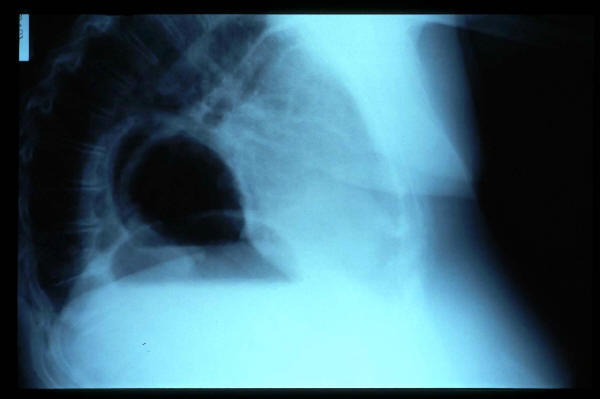

Paquipleuritis. Fractura costal.